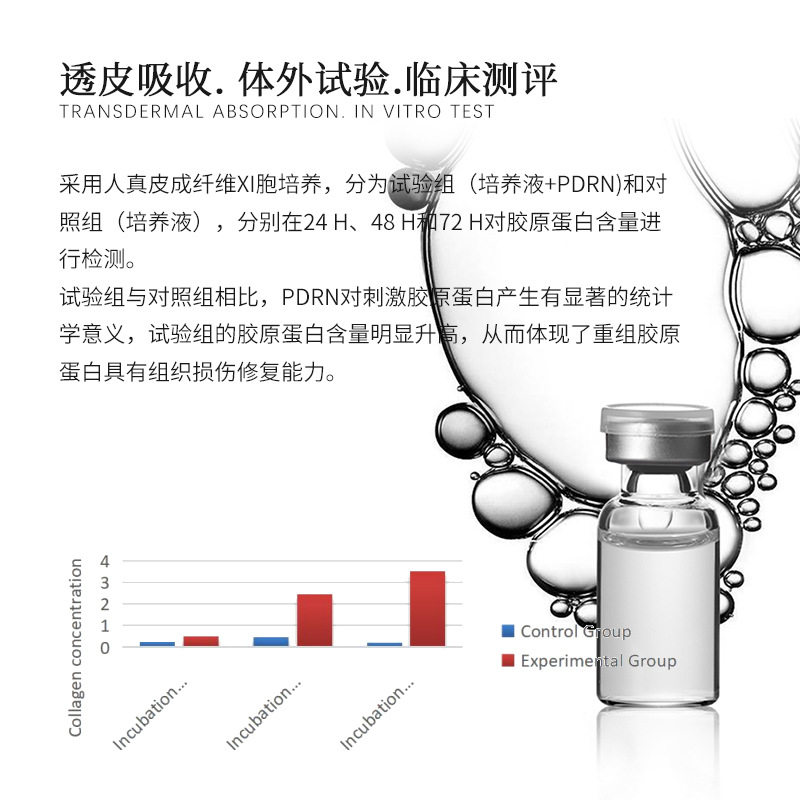

Pdrn Salmon Essence Dna Sodium Lightens Wrinkles, Brightens Skin, Revitalizes Skin Care, Classy Hydrating Set, Exclusively for Beauty Salons

| Product name | Salmon water light essence |